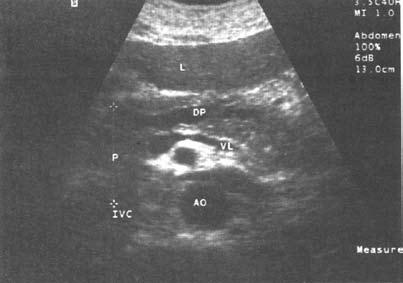

Ультразвуковое исследование (сканирование) является одним из наиболее информативных и притом неинвазивных методов исследования ПЖ и должно осуществляться во всех случаях, когда подозревается ее патология (рис. 137–139).

Датчик располагается в эпигастральной области и его перемещают соответственно проекции железы на области левого и правого подреберий. В норме ПЖ имеет ровные, четкие контуры и гомогенную структуру, а диаметр главного панкреатического протока не превышает 1,5–2 мм. При патологии может выявляться общее увеличение размеров органа с равномерным уменьшением эхоплотности, свидетельствующее об отеке. Уменьшение размеров железы, неоднородность структуры, наличие мелких участков уплотнения ткани, а также нечеткость контуров могут говорить о фиброзных изменениях в железе, а небольшие резко выраженные эхоположительные узелки – об очаговом обызвествлении паренхимы. Эхоструктуры высокой плотности, расположенные в протоке и дающие феномен «ультразвуковой дорожки», являются признаком внутрипротоковых конкрементов. Жидкостные образования (ложные кисты, вялотекущие абсцессы) представляются на эхограмме округлыми участками значительно пониженной эхоплотности с более или менее четкими контурами и дорсальным усилением. Хорошо сформированные ложные кисты с жидким содержимым имеют округлую или овальную форму, гомогенны и окружены четко выраженной капсулой. Содержимое несформировавшихся кист и абсцессов может быть неоднородным из‑за наличия в них, помимо жидкости, тканевых секвестров и детрита.

Рис. 137. Хронический панкреатит. Расширение протока поджелудочной железы (DP). L – печень; Р – поджелудочная железа; VL – селезеночная вена; IVC – нижняя полая вена; АО – аорта

К сожалению, и специальные методы не во всех случаях позволяют решить рассматриваемую дифференциально‑диагностическую задачу. Так, исследование крови больного на карбогидратный антиген (СА19‑9) и раковый эмбриональный антиген (РЭА) дает отчетливо положительный ответ лишь при достаточно больших размерах опухоли, часто в неоперабельных случаях. Исследование ПЖ с помощью ультразвука или на компьютерном томографе дает увеличение размеров железы, в особенности ее головки, и при ХП, и при раке, а также выявляет очаговые образования тех или иных размеров, причем для рака более характерно одиночное гипоэхогенное образование, а при ХП поджелудочная железа чаще изменена диффузно, она гиперэхогенна (более плотная), содержит множественные кальцификаты (см. рис. 137–139), хотя точно дифференцировать характер очагов удается далеко не во всех случаях. Трудности дифференциальной диагностики ХП и рака ПЖ по данным УЗИ и КТ иллюстрируют рисунки 142–145.